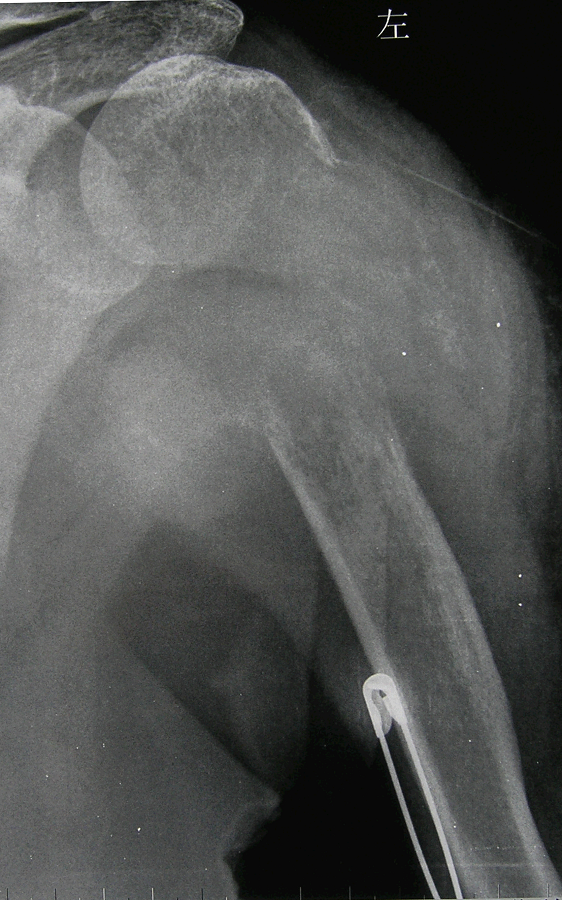

2.病例2:女 52岁,左肱骨近端肝癌骨转移并病理性骨折,术前穿刺活检确诊后行肿瘤广泛切除定制型假体置换术(原发瘤已手术)。

图7 术前X线片